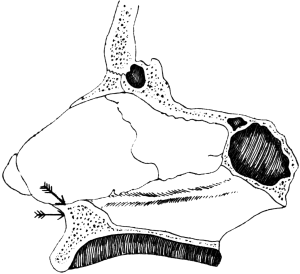

| 315. | Incisions for Lateral Rhinotomy (Moure’s Operation) | 619 |

| 316. | The Area of Bone removed in Lateral Rhinotomy | 619 |

| 317. | Lateral Rhinotomy | 620 |